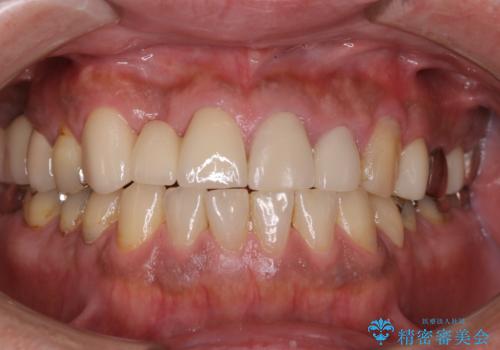

タバコによるヤニをPMTCで除去